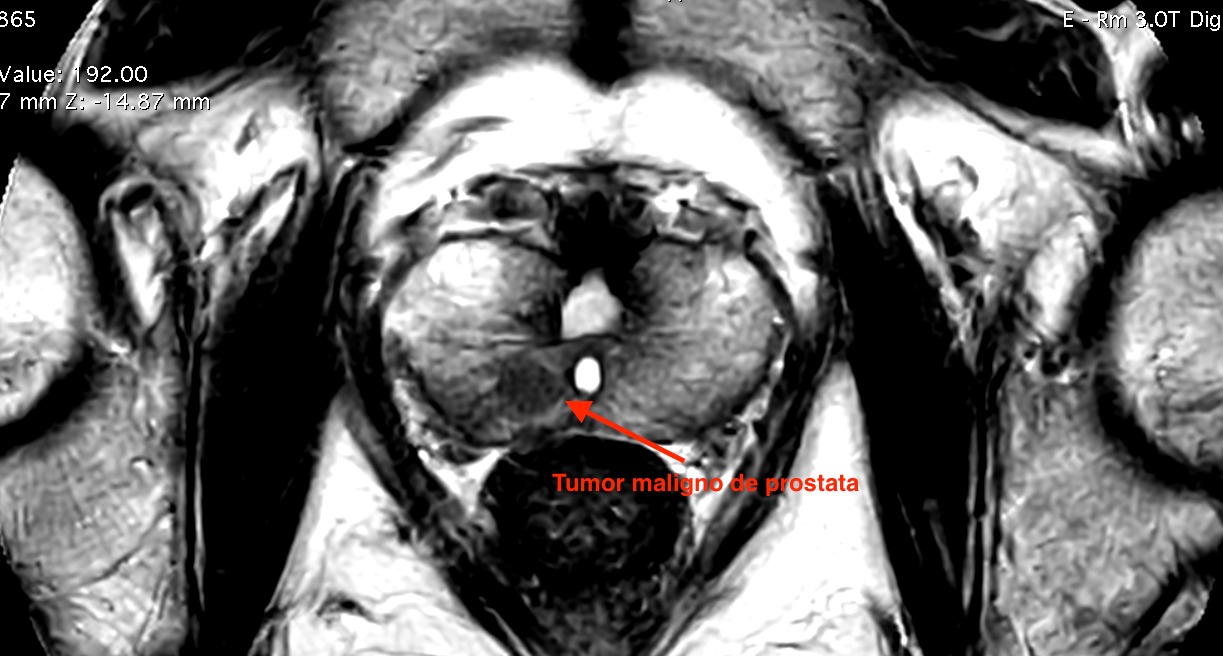

La terapia focal prostática es un tratamiento mínimamente invasivo que destruye únicamente la zona donde se encuentra el tumor, sin retirar toda la próstata.

A diferencia de la prostatectomía radical, que elimina completamente la glándula, la terapia focal:

En otras palabras, busca controlar el cáncer sin afectar innecesariamente estructuras clave